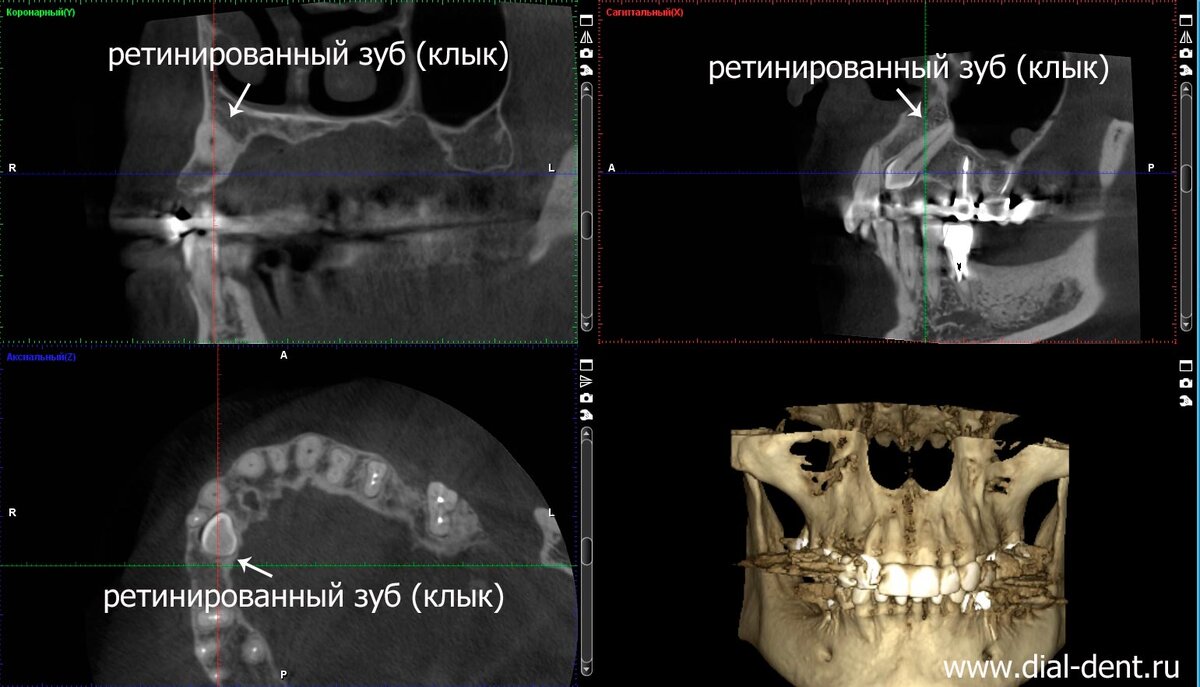

В процессе консультации выполнена компьютерная томография зубов, чтобы всесторонне изучить ситуацию с зубами и костной тканью.

По результатам КТ выявились дополнительные проблемы:

— наличие ретинированного (залегавшего в кости) клыка на верхней челюсти, в области, куда планировалась установка импланта;

на компьютерной томограмме зубов виден ретинированный (не выросший) клык в толще кости